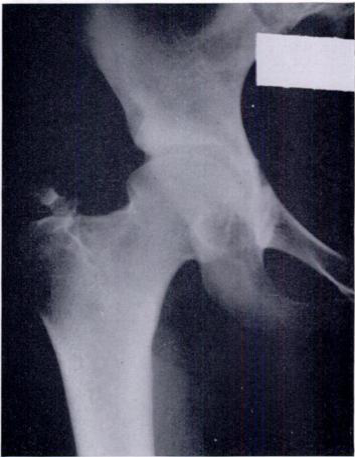

Reduced right femoral head after capsular interposition

Reduced right femoral head several years after reaming an acetabulum and capsular interposition.